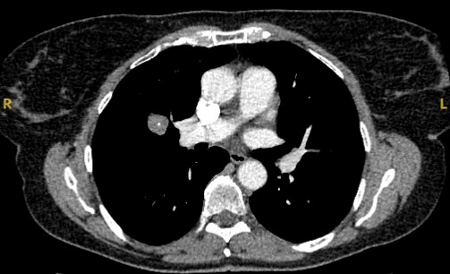

Computed tomography (CT) showing a left upper lobe peripheral nodule with several pleural ‘tags’ and element of retraction of the adjacent pleura. Resection histopathology confirmed a well-differentiated squamous cell lung cancer

From the collection of Dr George Tsaknis, MD, PhD, FRCP(London), MRQA, MAcadMEd, PGCert; used with permission